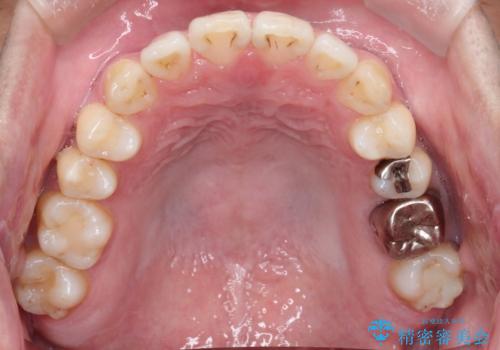

- 前歯の出ているのが気になる、下唇を噛んで痛いとのことで来院された患者様です。マウスピース矯正をご希望でした。

奥歯の噛み合わせはしっかりしていましたので、奥歯の動きは最小限にし、前歯の並びに集中した治療計画+インビザラインのシミュレーションを作成しました。

奥歯の噛み合わせは整っていたため、前歯の並びを美しく修正することに専念できました。マウスピース矯正による治療で短期間で改善しました。